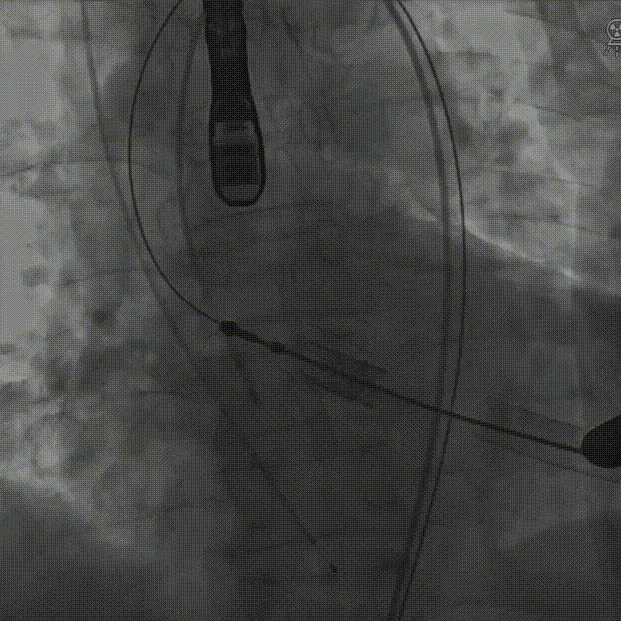

定位件入窦后造影:

降落瓣膜件:

140bpm快速起搏下释放瓣膜:

复查根部造影,未见明显反流: